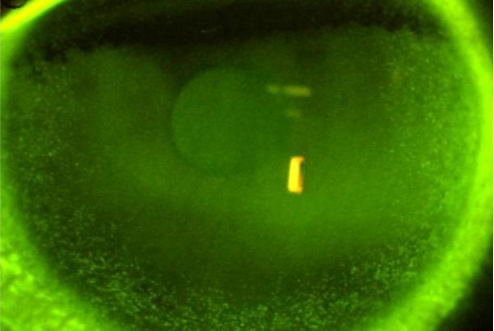

Diagnosis: Fluorescein staining reveals linear branching patterns with terminal bulbs.

Herpetic Keratitis

Fluorescein staining reveals dendritic lesions (linear branching patterns with terminal bulbs) or geographic ulcers associated with the herpes simplex virus (HSV). The edges may be slightly elevated due to swollen epithelial cells.

Symptoms include eye pain, corneal injection, visual changes (blurry vision, decreased visual acuity), tearing, discharge, photophobia.